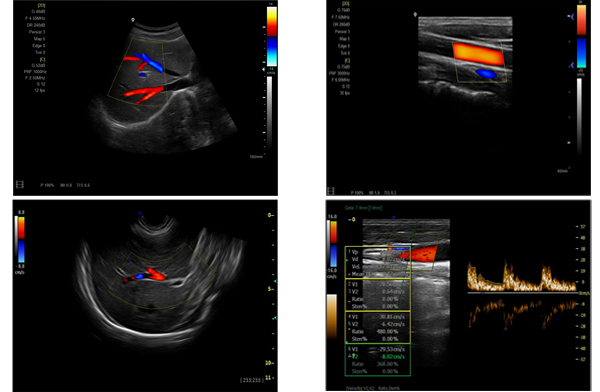

為高集成數(shù)字式彩色多普勒系列產(chǎn)品之一,廣泛實施于腹部,產(chǎn)科,婦科,血管,小器官,泌尿,新生兒和兒科等臨床,屬全身應(yīng)用型彩色多普勒儀器。

●全身應(yīng)用型包含2D/CFM/PDI/PW/ M等掃描模式;